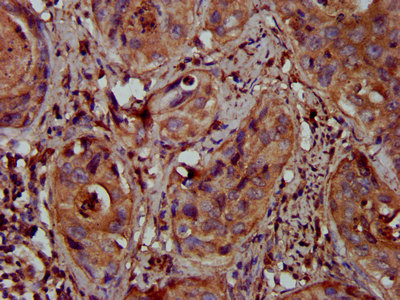

ApplicationELISA, IHC; Recommended dilution: IHC: 1:200-1:500